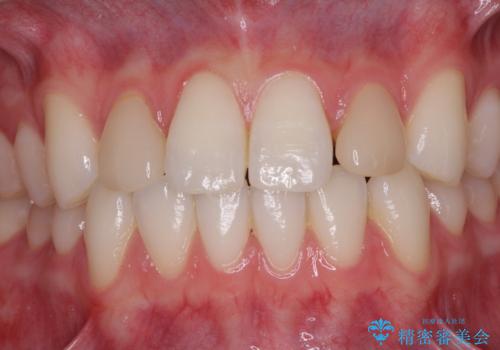

- 前歯のラミネートベニアの不自然な色合いを気にして来院された患者様です。

矯正治療後戻り防止のワイヤー周りにむし歯があったため、オールセラミッククラウンにて補綴することとしました。